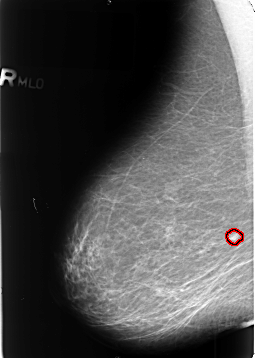

B_3402_1.RIGHT_MLO

RIGHT_MLO LINES 4648 PIXELS_PER_LINE 3304 BITS_PER_PIXEL 12 RESOLUTION 50 OVERLAY

FILE: B_3402_1.RIGHT_MLO.OVERLAY

TOTAL_ABNORMALITIES 1

ABNORMALITY 1

LESION_TYPE MASS SHAPE OVAL MARGINS ILL_DEFINED

ASSESSMENT 4

SUBTLETY 4

PATHOLOGY MALIGNANT

TOTAL_OUTLINES 1

BOUNDARY